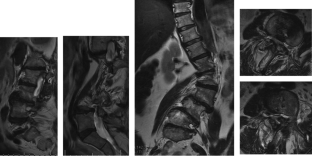

Fig. 1